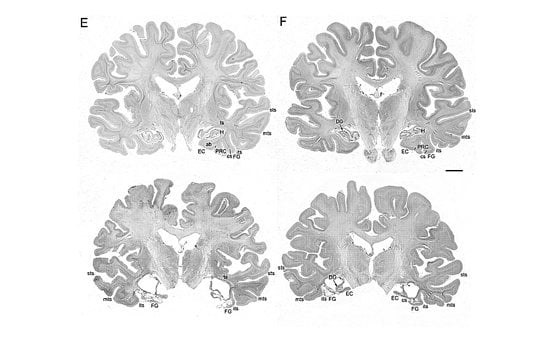

These photomicrographs depict comparative stained sections of a healthy brain (top) and of patient EP, in which significant structures in the medial temporal lobe are heavily damaged or missing. The letters identify specific brain structures, such as EC and PRC for entorhinal cortex and perirhinal cortex, respectively, both important to memory formation and function. Credited to UCSD.

After his death, EP’s brain was also processed at The Brain Observatory. The last five years have been spent parsing the data and painting a full picture of what happened to EP and why. Squire said EP’s viral encephalitis infection wreaked havoc upon his brain: Large, bilateral, symmetrical lesions were found in the medial temporal lobe, portions of the brain responsible for formation of long-term memory; and whole, crucial structures were eliminated – the amygdala and hippocampus among them. Additionally, other brain regions had atrophied and white matter – the support fibers that transmit signals between brain structures – had become gliotic or scarred.